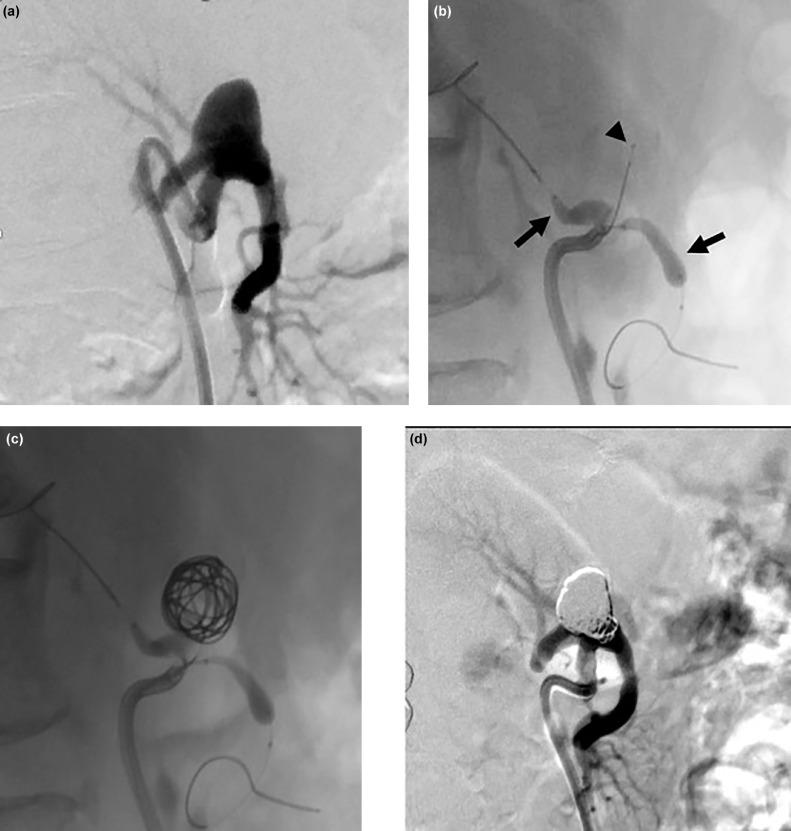

Here, we report the case of a 59-year-old male patient who underwent transcatheter embolization of bilateral renal artery aneurysms, using 2 microballoons and 1 microcatheter, all carried within a single guiding sheath. During coil embolization in a visceral artery, there are situations that can require multiple microdevices. We developed a new 6-Fr Shephard-hook type guiding sheath (Parent Plus 60) with a lumen large enough to deliver three microdevices simultaneously. This technique can be used broadly in different clinical scenarios, and it may provide novel treatment strategies to clinicians in the future.

在此,我们报告一例59岁男性患者的病例,该患者接受了双侧肾动脉瘤的经导管栓塞术,使用了2个微球囊和1个微导管,所有这些都通过单个引导鞘输送。在内脏动脉进行弹簧圈栓塞时,有时可能需要多个微型器械。我们研发了一种新型的6F Shepherd钩型引导鞘(Parent Plus 60),其管腔足够大,能够同时输送三个微型器械。该技术可广泛应用于不同的临床场景,未来可能为临床医生提供新的治疗策略。